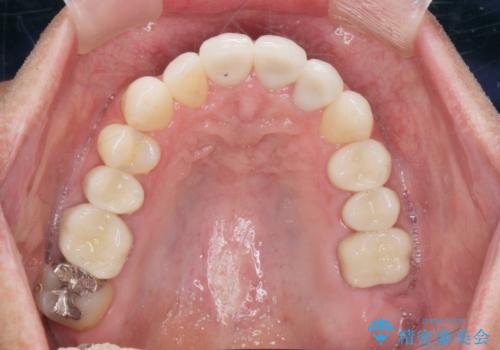

矯正と虫歯のセラミック治療 総合歯科治療の実践

- 突き出た前歯の角度の改善と虫歯治療の改善を求めて来院されました。

虫歯を除去したのち、マウスピース矯正治療を行い、歯並びやがたつきを改善したのち、セラミックに置き換えることで審美性の向上を計画します。